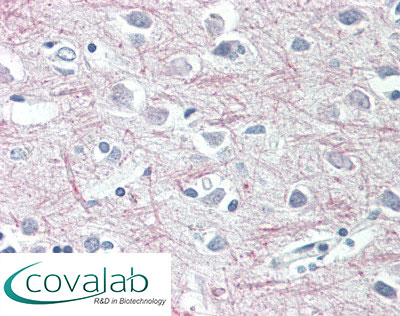

Anti-TAOK1 antibody IHC staining of formalin-fixed, paraffin-embedded human cortex after heat-induced antigen retrieval.

Anti-TAOK1 antibody IHC staining of formalin-fixed, paraffin-embedded human cortex after heat-induced antigen retrieval.